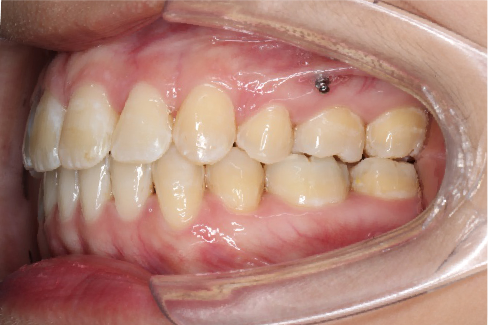

• 磨牙,尖牙I类关系,中线齐

IntraoralExamination(2016-08.31,Wu)

2018.11.14  术后磨牙尖牙I类关系,中线齐,覆合,覆盖正常